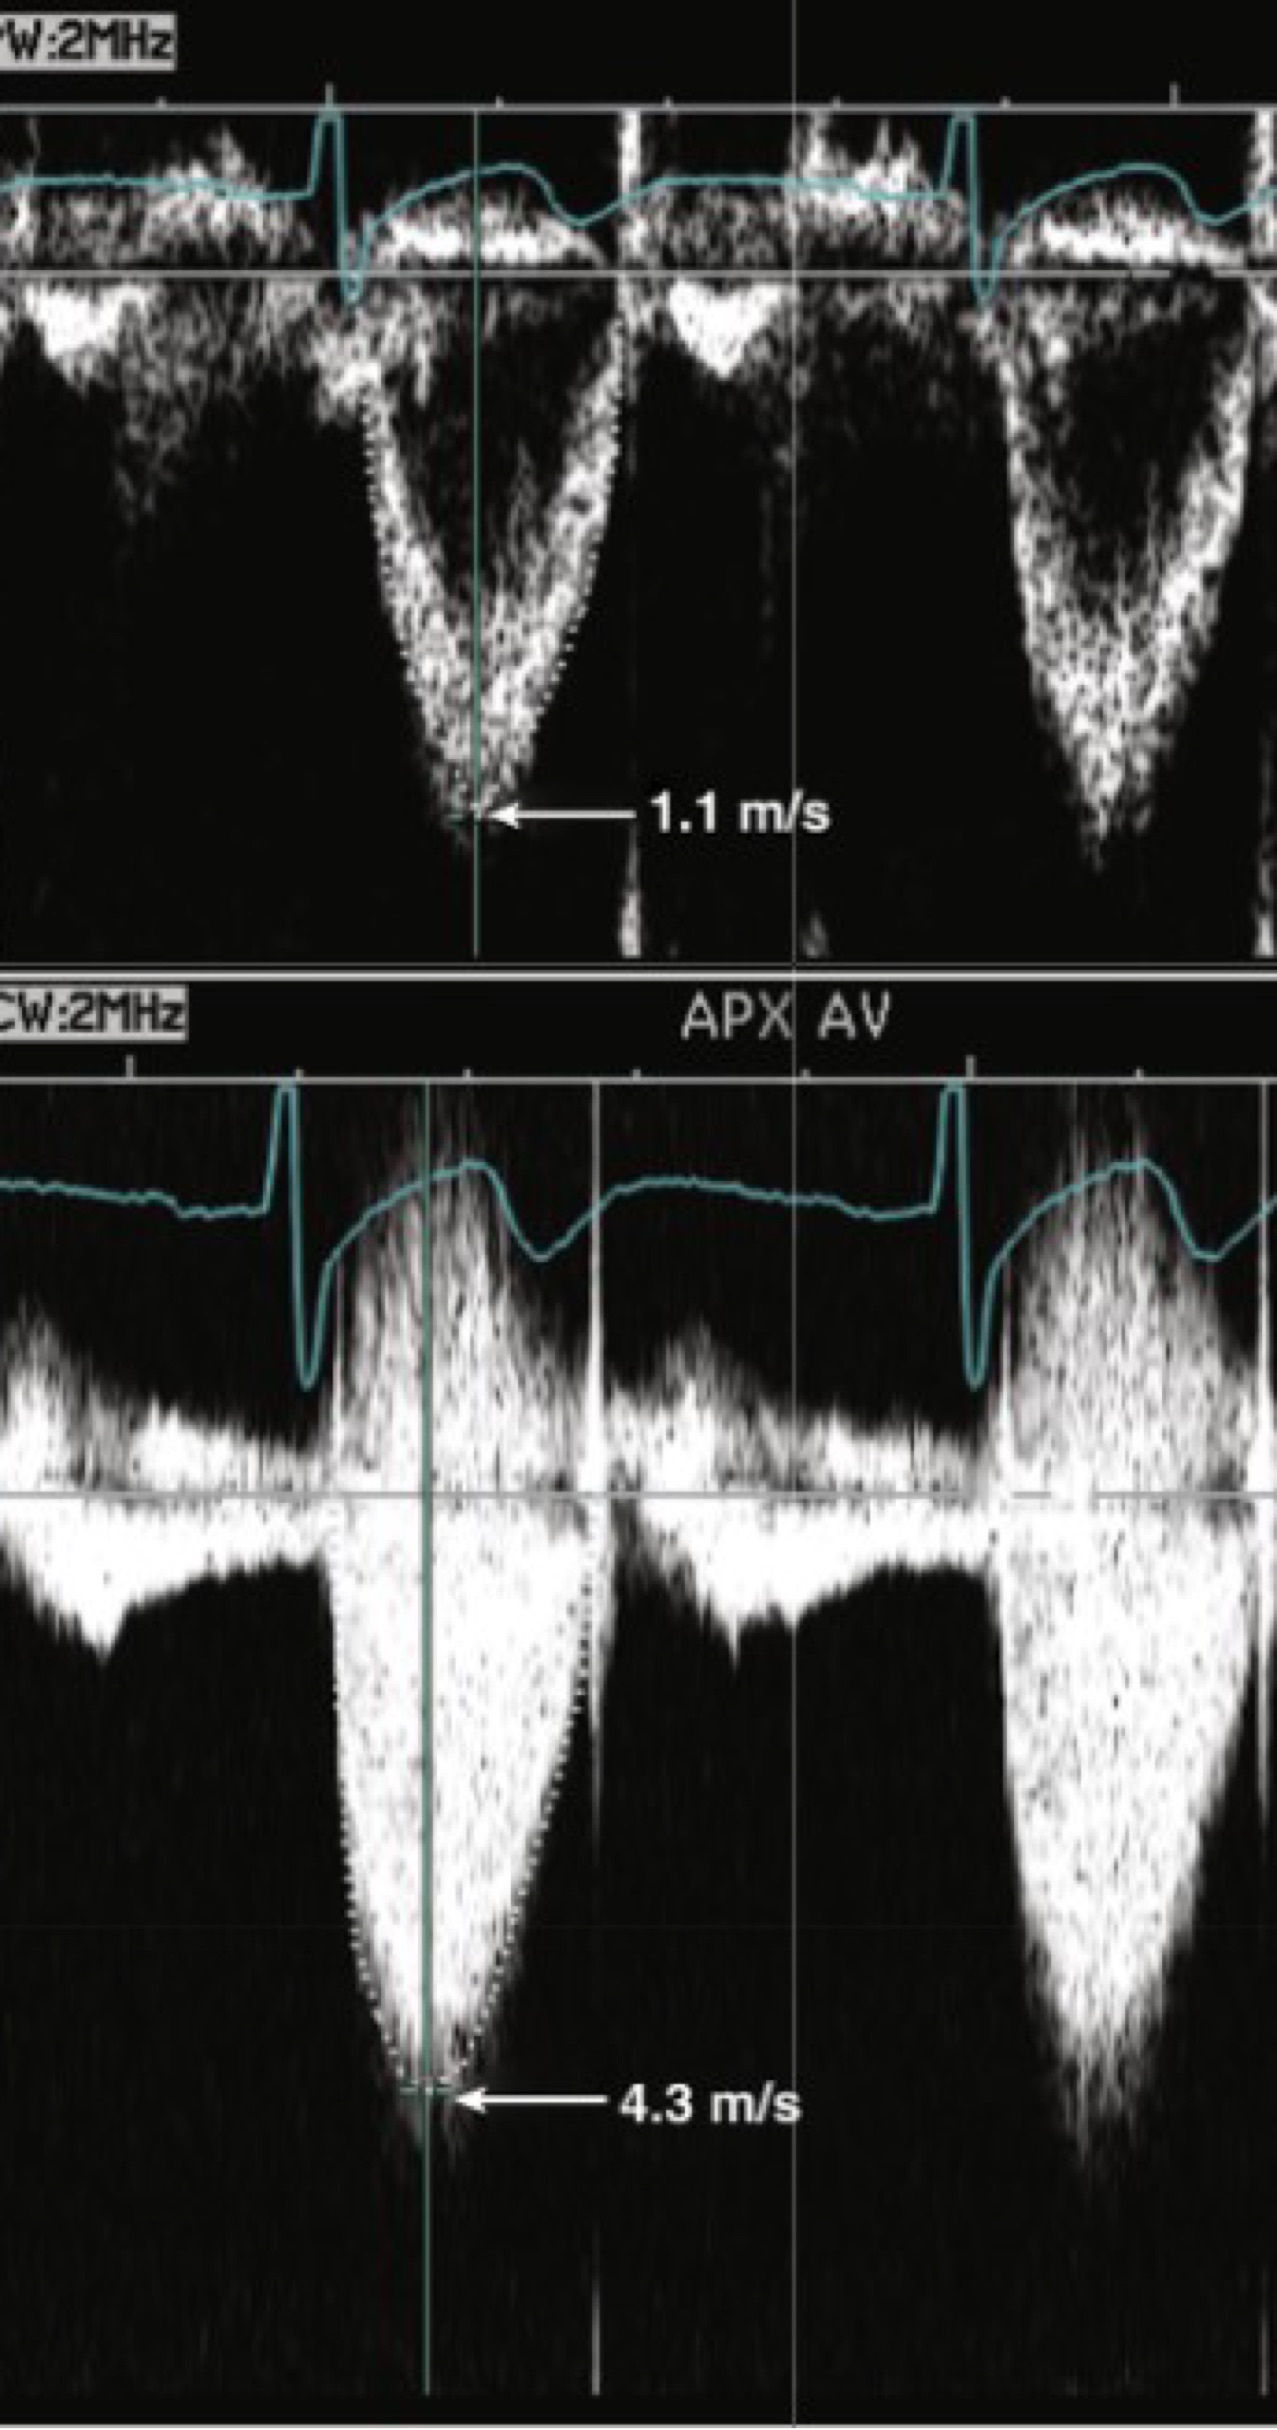

Which window has this pedoff CW waveform been taken from?

Apical

(This is severe stenosis, because it is over 4cm/s)

What is the grade of stenosis by peak velocity and velocity ratio?

Peak AV velocity is severe; velocity ratio is moderate

Velocity ratio LVOT/AV = 1.1/4.3 = 0.26

Velocity ratio severe = <0.25

Moderate 0.25- 0.5

Mild = >0.5